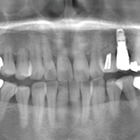

- 歯周病および根尖病巣により骨吸収、動揺が激しく、抜歯適応の歯牙に対し非外科的に歯周治療をNd:YAGレーザーを用いて行い、歯牙の保存を試みた症例

- 症例2:痛くて噛めない、歯がグラグラする、口臭が気になる